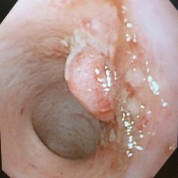

慢性的な下痢、血便、腹痛やしぶりなどの症状から大腸の病気が疑われる場合、原因を確認する為に実施します。 主に癌やポリープ、炎症性疾患の発見を目的としています。多くの場合確定診断をする為に、組織を一部採取して病変が良性か悪性かの鑑別を含めた組織診断を 実施します。

炎症性ポリープ

消化器型リンパ腫